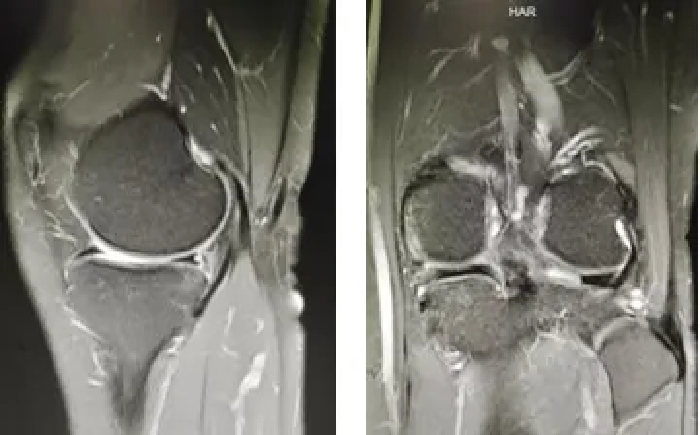

麻醉下查体:再次术前确认ACL损伤

为了确保手术万无一失,李忠教授带领团队成员与北京清华长庚医院余家阔教授及机器人工程师团队共同召开术前会议,术前进行了多次“数字化预演”,为手术的顺利实施奠定了坚实基础。

10月25日,手术由李忠教授、刘俊才副教授及团队成员联合完成,全程误差控制在亚毫米级。术中运用先进的关节镜技术与机器人辅助系统,通过高精度影像导航,实现胫骨与股骨骨道的精准定位。机器人精准规划与机械臂稳定操作的结合,使自体肌腱移植一次性成功,不仅显著缩短手术时间,还降低了术中出血与组织损伤,对受损的交叉韧带及半月板进行了“完美修复”。